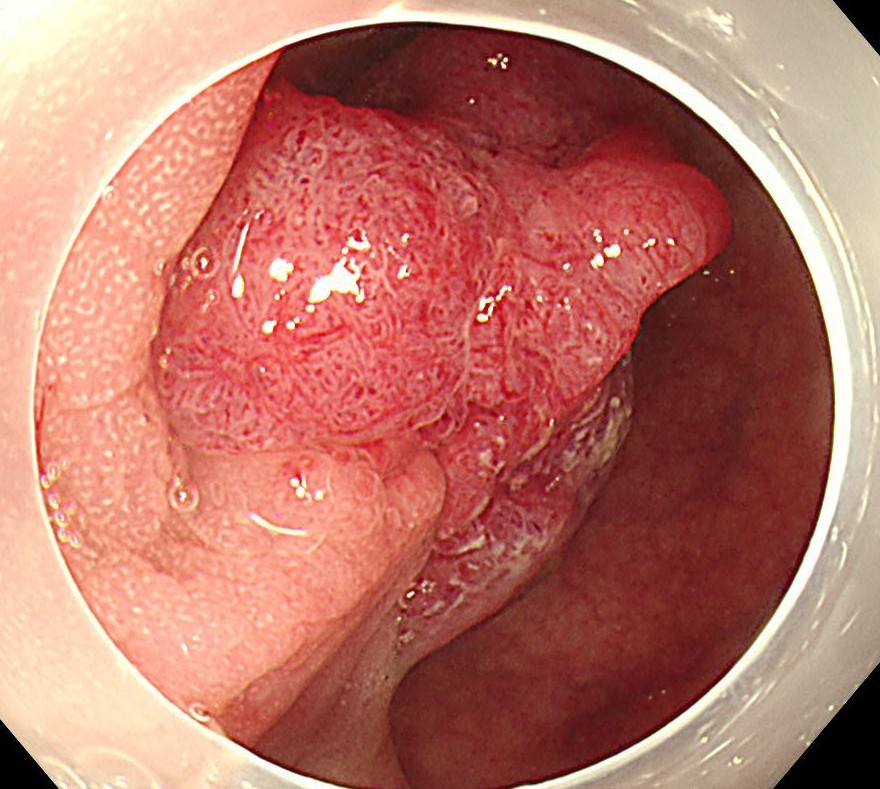

狭帯域光観察(NBI)では明らかにV型パターンであり、悪性を疑いますが、内視鏡治療可能と診断しました。